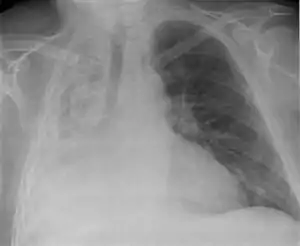

| Atelectasis of a person's right lung | |

Clinically significant atelectasis is generally visible on chest X-ray; findings can include lung opacification and/or loss of lung volume. Post-surgical atelectasis will be bibasal in pattern. Chest CT or bronchoscopy may be necessary if the cause of atelectasis is not clinically apparent. Direct signs of atelectasis include displacement of interlobar fissures and mobile structures within the thorax, overinflation of the unaffected ipsilateral lobe or contralateral lung, and opacification of the collapsed lobe. In addition to clinically significant findings on chest X-rays, patients may present with indirect signs and symptoms such as elevation of the diaphragm, shifting of the trachea, heart and mediastinum; displacement of the hilus and shifting granulomas.[10]

Atelectasis of the right lower lobe seen on chest X-ray.